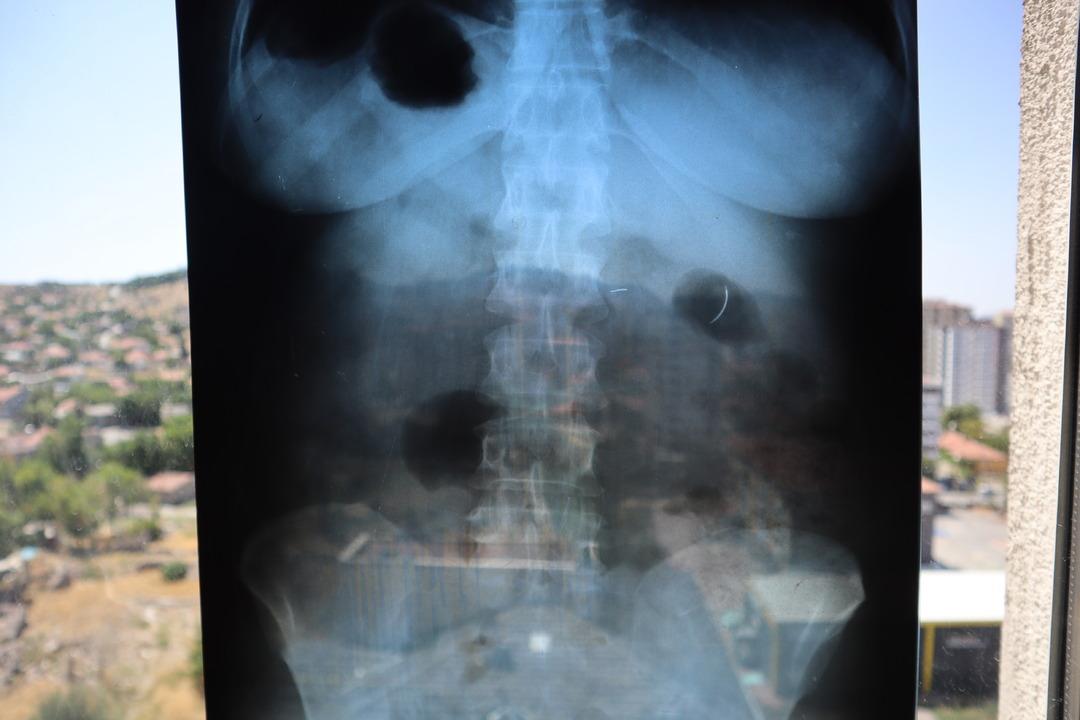

Kentte yaşayan 2 çocuk annesi Ayhan Tanyıldız, 2003 yılında karaciğerindeki kist nedeniyle ameliyat oldu. Ameliyat olduktan 6 yıl sonra böbrek rahatsızlığı nedeniyle hastaneye giden Tanyıldız’ın çekilen röntgeninde iğne görüldü. Tanyıldız’ın kist ameliyatı sırasında karnında ameliyat iğnesi unutulduğu ortaya çıktı. Kendisini özel hastanede ameliyat eden Genel Cerrahi Doktoru İ.D.’ye dava açan Tanyıldız, ağrılarının nedeninin karnında unutulan ameliyat iğnesi olduğunu öğrendi.

19 yıl sonra mahkemesi de sonuçlanan Tanyıldız, bir miktar tazminat almaya hak kazandı. 22 yıldır ameliyat iğnesiyle yaşayan Tanyıldız, “2003 yılında ameliyatım yapıldı. Karaciğerimdeki kistten dolayı ameliyat oldum. Karaciğerimde kist oluşmuş. Kisti alırken ameliyat iğnesini unutmuşlar. 6 yıl sonra fark ettim. İlk öğrendiğimde başka doktora gittim, böbreklerimden rahatsızlanmıştım. Doktor film çekince ‘sen MR’a girme, ciğerinde iğne var’ dedi. O zaman fark ettim. Fiziksel olarak hala ağrısını, yıllardır çekiyorum” diye konuştu.

MR cihazına giremediğinden ve günlük hayatındaki engellerinden bahseden Tanyıldız, “Yaşayan ölü gibiyim. Psikolojim bozuldu, kendime gelemedim. Hala o ağrıyla yaşayan ölü gibiyim. MR’a da giremiyorum, hiçbir derdimi sonuçlandıramıyorum. Yürürken nefes nefese kalıyorum, korse takıyorum. Çünkü korse takmadan hızlı yürüyemiyorum, adeta batıyor. Hiçbir hastalığımı sonuçlandıramıyorum, sağlık sorunum var” dedi.

Yaşanan süreçte ailesinin psikolojik sorunlar yaşadığını kaydeden Tanyıldız, “Tehlikeli olduğu için, benim gözüme baktıkça arkalarını dönüp ağlıyorlardı. Ben yaşayan ölü gibiyim, canlı bomba gibi geziyorum. Sırtıma bir top çarpsa ya da arabaya bindiğimde fren yapılsa, yürürken düşsem, ciğerimin patlama ihtimali var. Hukuki yola başvurdum, gereken tazminatımı aldım. Hastalar ameliyat olmadan önce dikkat etsinler, araştırsınlar. Doktorlarını iyi seçsinler, çünkü sonucu çok kötü. Yarım kalıyorsun onu tamamlayamıyorsun” ifadelerini kullandı.

Karnındaki iğneyi alacak doktor bulamadığını belirten Tanyıldız, şöyle konuştu: “İğne 22 yıldır çıkarılmadı. Riskli olduğu için çıkaramıyorlar. Kanamayı durduramayacakları için, iğne ciğerimde geziyor. Açınca iğneyi bulamayacakları için, kimse o riski almak istemiyor. İnşallah bir doktor çıkar. Beni bu sıkıntıdan, 22 yıllık çektiğim çilelerden kurtarırsa çok mutlu olurum, dua ederim.” (DHA)